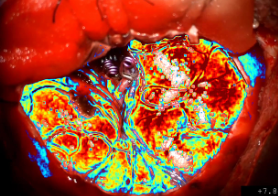

• National Institutes of Health (NIH) Centers of Biomedical Research Excellence (COBRE) for “Neuroimaging-guided Immunotherapy for Glioblastoma.” (PI: Miller)

• National Science Foundation (NSF) Seed Translational Research Project (STRP) for “Machine Learning for Real-time Detection of Complications during Neurosurgery.” (PI: Miller)

• American Cancer Society (ACS) Institutional Research Grant Pilot for “Intraoperative Surgical Guidance During Resection of Brain Tumors” (PI: Miller)